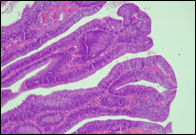

According to the degree of dysplasia, the premalignant lesions were described as follows: 106 (59.5%) with mild dysplasia, 48 (26.8%) with moderate dysplasia, and 24 (13.5%) with severe dysplasia. When grouped according to the WHO classification (2019), the premalignant lesions exhibited low-grade dysplasia in 154 (86.5%) patients and high-grade dysplasia in 24 (13.5%). Figure 6 shows different morphopathological forms of premalignant lesions from the series of patients included in the study.

A | B | C |

D | E | F |

Fig. 6 Morphological subtypes of conventional adenomas according to the WHO classification (2019) A, B – tubular adenoma with moderate epithelial dysplasia (A - HE stain, ×100; B - HE stain ×200); C – villous adenoma with moderate epithelial dysplasia (HE stain, x100); D – tubular adenoma with high epithelial dysplasia (HE stain, x200); E – tubulovillous adenoma with high epithelial dysplasia (HE stain, x200); F – tubulovillous adenoma with low epithelial dysplasia (HE stain, x200) | ||